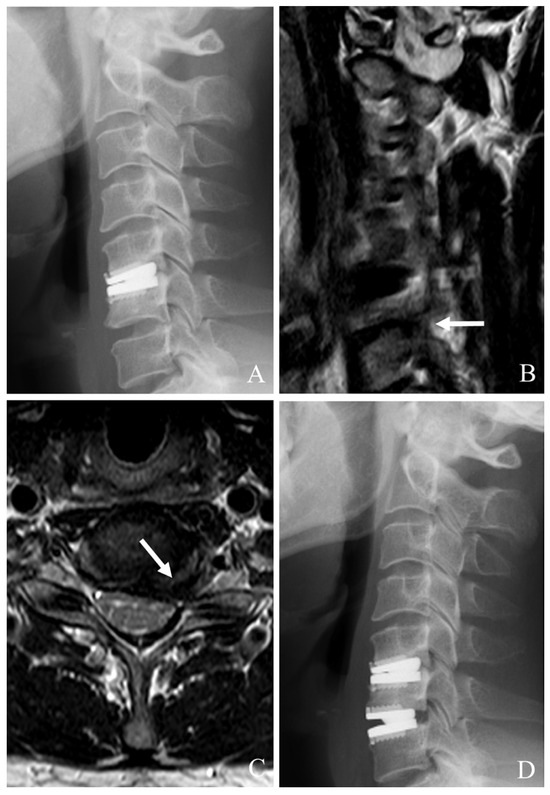

When CDA fails at the index level, PCDF is a well-established surgical option, particularly in cases where anterior reoperation is either contraindicated or insufficient [22,23,24,25,26]. PCDF provides robust neural decompression and stabilization, making it especially useful for cases with instability, deformity, or posterior element involvement (Figure 3). Although this approach is more invasive than anterior reoperations, it offers comprehensive management of those with complex failure mechanisms.

Figure 3. Plain X-rays (A), computed tomography (B), and magnetic resonance image (C) showing cervical disc arthroplasty at C5–6 and C6–7 and severe foraminal stenosis and posterior osteophytes (white arrows). The patient underwent C4–7 posterior cervical laminectomy, foraminotomy, and fusion with C3–7 pedicle screw fixation (D).